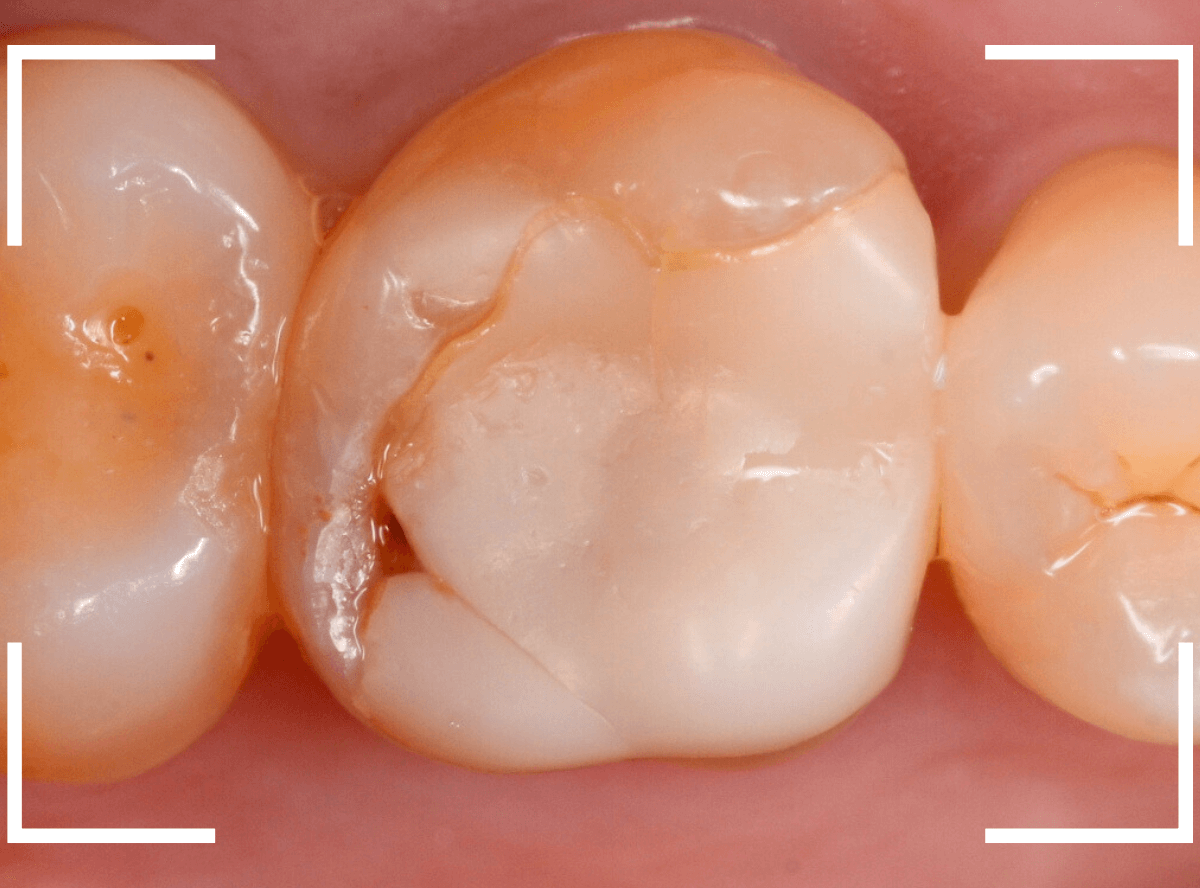

Case.20 破折したセラミックの再製作

今回は、過去に治療したセラミックが割れてしまったという患者さんのケースです。

歯の噛み合わせの部分にひびが入ってしまっているのがわかります。

4-5年前に治療したとの事でしたが、さすがにセラミックですので見た目の劣化もなかったので残念ですね。

インレーを除去して確認します。

セラミックが割れてしまった部分は割れづらくするために歯の形を再トリミングするのですが、今回はあまり修正できる部分がない、との判断で、より硬いジルコニア・インレーでの再製作となりました。

模型上で精密に製作します。

set後の写真です。

E-MAXなどに比べ、色調再現性に劣るジルコニア・インレーですが、除去前と遜色ない審美性でsetできたかと思います。